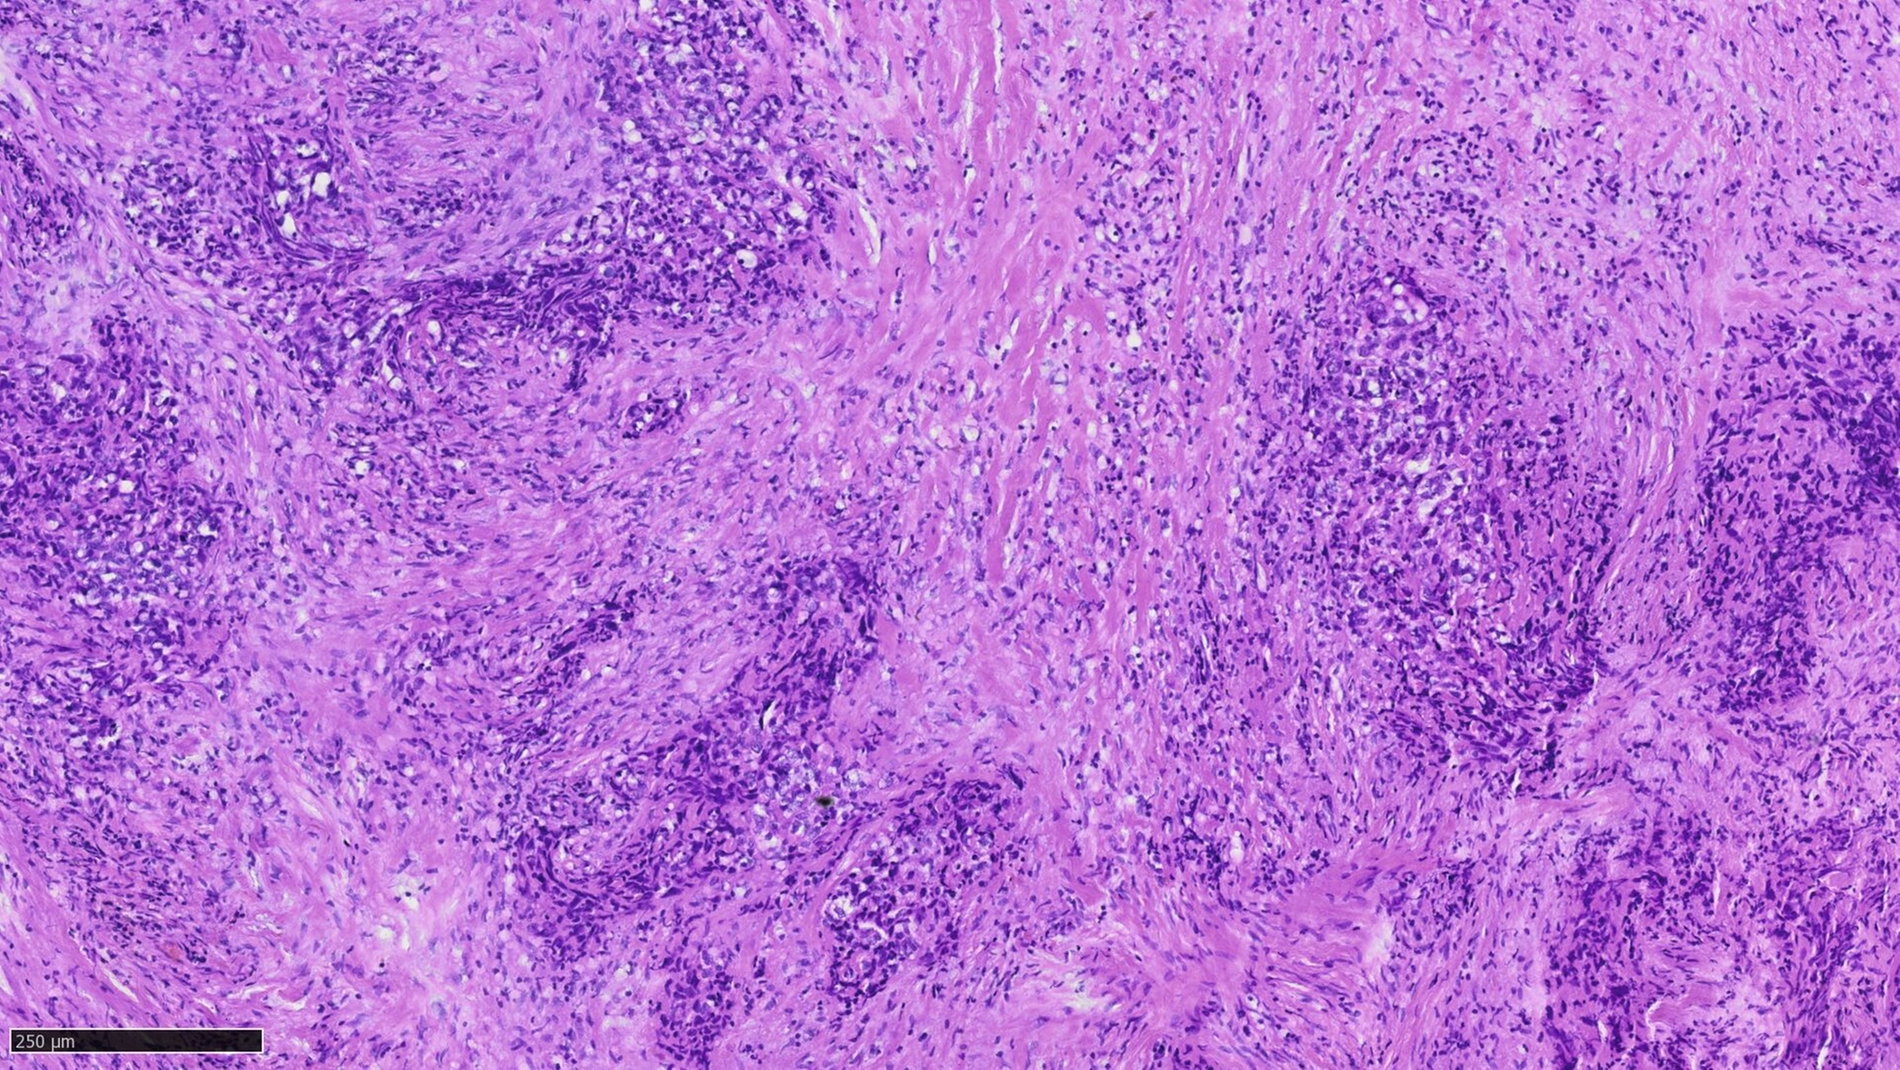

Bei der histopathologischen Untersuchung des Präparats zeigten sich allerdings neben fibrosierten, entzündlich infiltrierten Weichgewebeanteilen atypische, suspekte Epithelien in Stroma-invasiver Konfiguration, die sich in der ergänzenden immunhistochemischen Aufbereitung mit Antikörpern positiv gegen Zytokeratin 5 und 6, Panzytokeratin und p40 kontrastierten. Zudem erwies die supplementäre Untersuchung mit Antikörpern gegen den Proliferationsmarker Ki67 eine deutlich gesteigerte Zellproliferation im Bereich der oben beschriebenen suspekten Epithelanteile. In der Gesamtschau sprachen die vorliegenden Befunde abschließend für die Manifestation eines Stroma-invasiven, intraossären Plattenepithelkarzinoms. Der Befund wurde wiederholt gemeinsam mit den untersuchenden Pathologen diskutiert und abschließend im Sinne eines Sechs-Augen-Prinzips bestätigt (Abbildung 3).